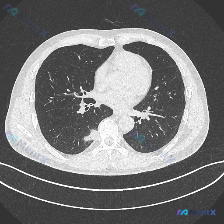

整理了一份影像读片讨论材料,核心问题是:这个胸部CT肺窗横断面,原提问认为异常是「空气腔隙浑浊(肺实变)」,但实际读片下来,核心异常是弥漫性分布的边界相对清晰的粟粒样小结节,分布广泛覆盖双肺上野,大小均一,没有看到明显的大片实变影、空洞或纤维条索。 这份病例值得讨论的点: 1. 为什么一开始说的「肺...